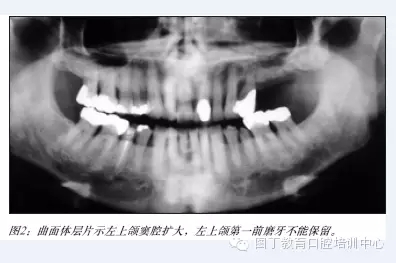

據(jù)筆者可獲得的有限的研究表明:術(shù)者經(jīng)過專業(yè)培訓(xùn),選擇適當(dāng)?shù)牟±?,上頜竇提升植骨術(shù)是一項(xiàng)成熟的種植外科技術(shù)(見圖2-6),種植體植入移植骨后的五年成功率達(dá)到95%以上。